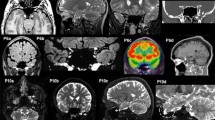

Figure 4 shows AA’s performance in drawing from memory, demonstrating, beyond some slight deformations on the right side, the global preservation of AA’s access to stored visual representations. Ten healthy subjects (7 F, 3 M; mean age = 32.3 years, SD = 4.32, range 26–39, and mean education = 18.70 years, SD = 2.31, range 15–22) correctly recognized AA’s drawings from memory (100% agreement, except for the drawing of a “glass”, whose agreement was 90%).

Furthermore, spared semantic access was demonstrated by AA’s preserved ability in sorting pictures into categories, when the names of categories were supplied by the examiner, similarly to what occurred for patient AB (Luzzatti et al. 1998). When presented with 32 pictures, one at a time, and asked to categorize each item according to three classes (animals, vegetables, and tools), she performed flawlessly (score 32/32; see Table 2E).

Interim discussion. We described the case of a patient, AA, suffering from modality-specific deficit in naming line drawings and real objects from sight with much better tactile naming and spared naming to definition (Section A). Her naming deficit from visual modality was not caused by early identification problems, since AA was able to analyze visually presented stimuli adequately (Section B). Seemingly, unimpaired performance on the reality decision task indicates that AA was able to access the structural description of objects (Section C). AA performed flawlessly on a word-to-picture matching task and was able to draw objects from memory from verbal stimuli (Section D). The relatively accurate performance on these tasks indicates that AA was able to process visual knowledge of objects from verbal stimuli. Her minimal impairment on a word-to-picture matching task is consistent with that reported by Luzzatti et al. 1998 in a similar case of OA, but not with the performance of other OA cases (e.g., Beauvois 1982; Riddoch and Humphreys 1987), who were impaired on such task. Finally, naming of color patches was severely impaired, with spared comprehension of color names (name-to-color matching) and preserved object-color knowledge: this pattern of performance is in double dissociation with that observed in Luzzatti and Davidoff (1994), whose patient suffered from impaired retrieval of object-color knowledge with preserved color naming, and also confirms a relatively preserved access to stored visual knowledge of objects from the phonological input lexicon.